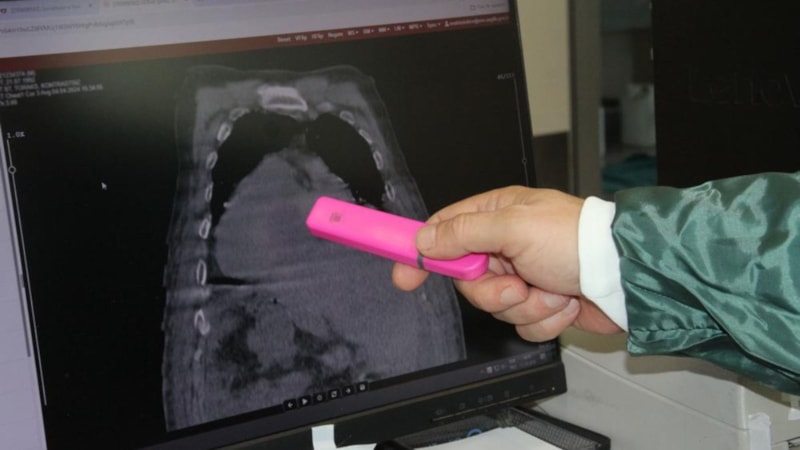

Giresun Eğitim ve Araştırma Hastanesi’nde görevli gastroenteroloji uzmanları, dünya tıp literatürüne geçecek çarpıcı bir keşfe imza attı. Gastroenteroloji Anabilim Dalı Başkanı Prof. Dr. Ahmet Cumhur Dülger, genetik temelli Polikistik Karaciğer Hastalığı (PCLD) ile birlikte, inflamatuvar bağırsak hastalıkları grubuna giren Ülseratif Kolit (ÜK) ve Crohn Hastalığı’nın (CH) aynı anda tek bir hastada görülmesinin, daha önce hiçbir bilimsel yayında rapor edilmediğini vurguladı.

Dülger, Giresunlu ve Ordulu iki kadın hastada bu sıra dışı üçlü hastalık tablosunun saptandığını belirterek, şunları söyledi:

Daha önce kayıtlara geçmemiş bu kombinasyonu detaylı bir şekilde analiz ederek bilimsel bir zemine oturttuk ve uluslararası camiaya sunduk. Hastaların memleketlerinden esinlenerek bu tabloyu ‘Karadeniz Sendromu’ olarak adlandırdık. Yaklaşık bir aylık sürede tanı koyduk, tedavi planladık, verileri doğruladık ve uluslararası İBH kongresine sunduk. Çalışmamız kabul gördü ve bilimsel çevrelerde yankı buldu.

Gastroenteroloji Uzmanı Dr. Öğr. Üyesi Gökhan Aydın ise Karadeniz Bölgesi'nde, özellikle Giresun çevresinde hem polikistik karaciğer hem de inflamatuvar bağırsak hastalıklarının oldukça sık görüldüğünü belirtti. Ancak bu hastalıkların birlikte varlığına çoğu zaman dikkat edilmediğini ifade eden Aydın, "Artık bu sendrom tıbben tanımlandı. Bu sayede tanı süreçleri daha sistematik hale gelecek, tedaviye dair daha net protokoller geliştirilebilecek. Ayrıca bu sendromun genetik arka planının ayrıntılı biçimde araştırılması da önümüzdeki dönemin önemli gündemlerinden biri olacak" dedi.